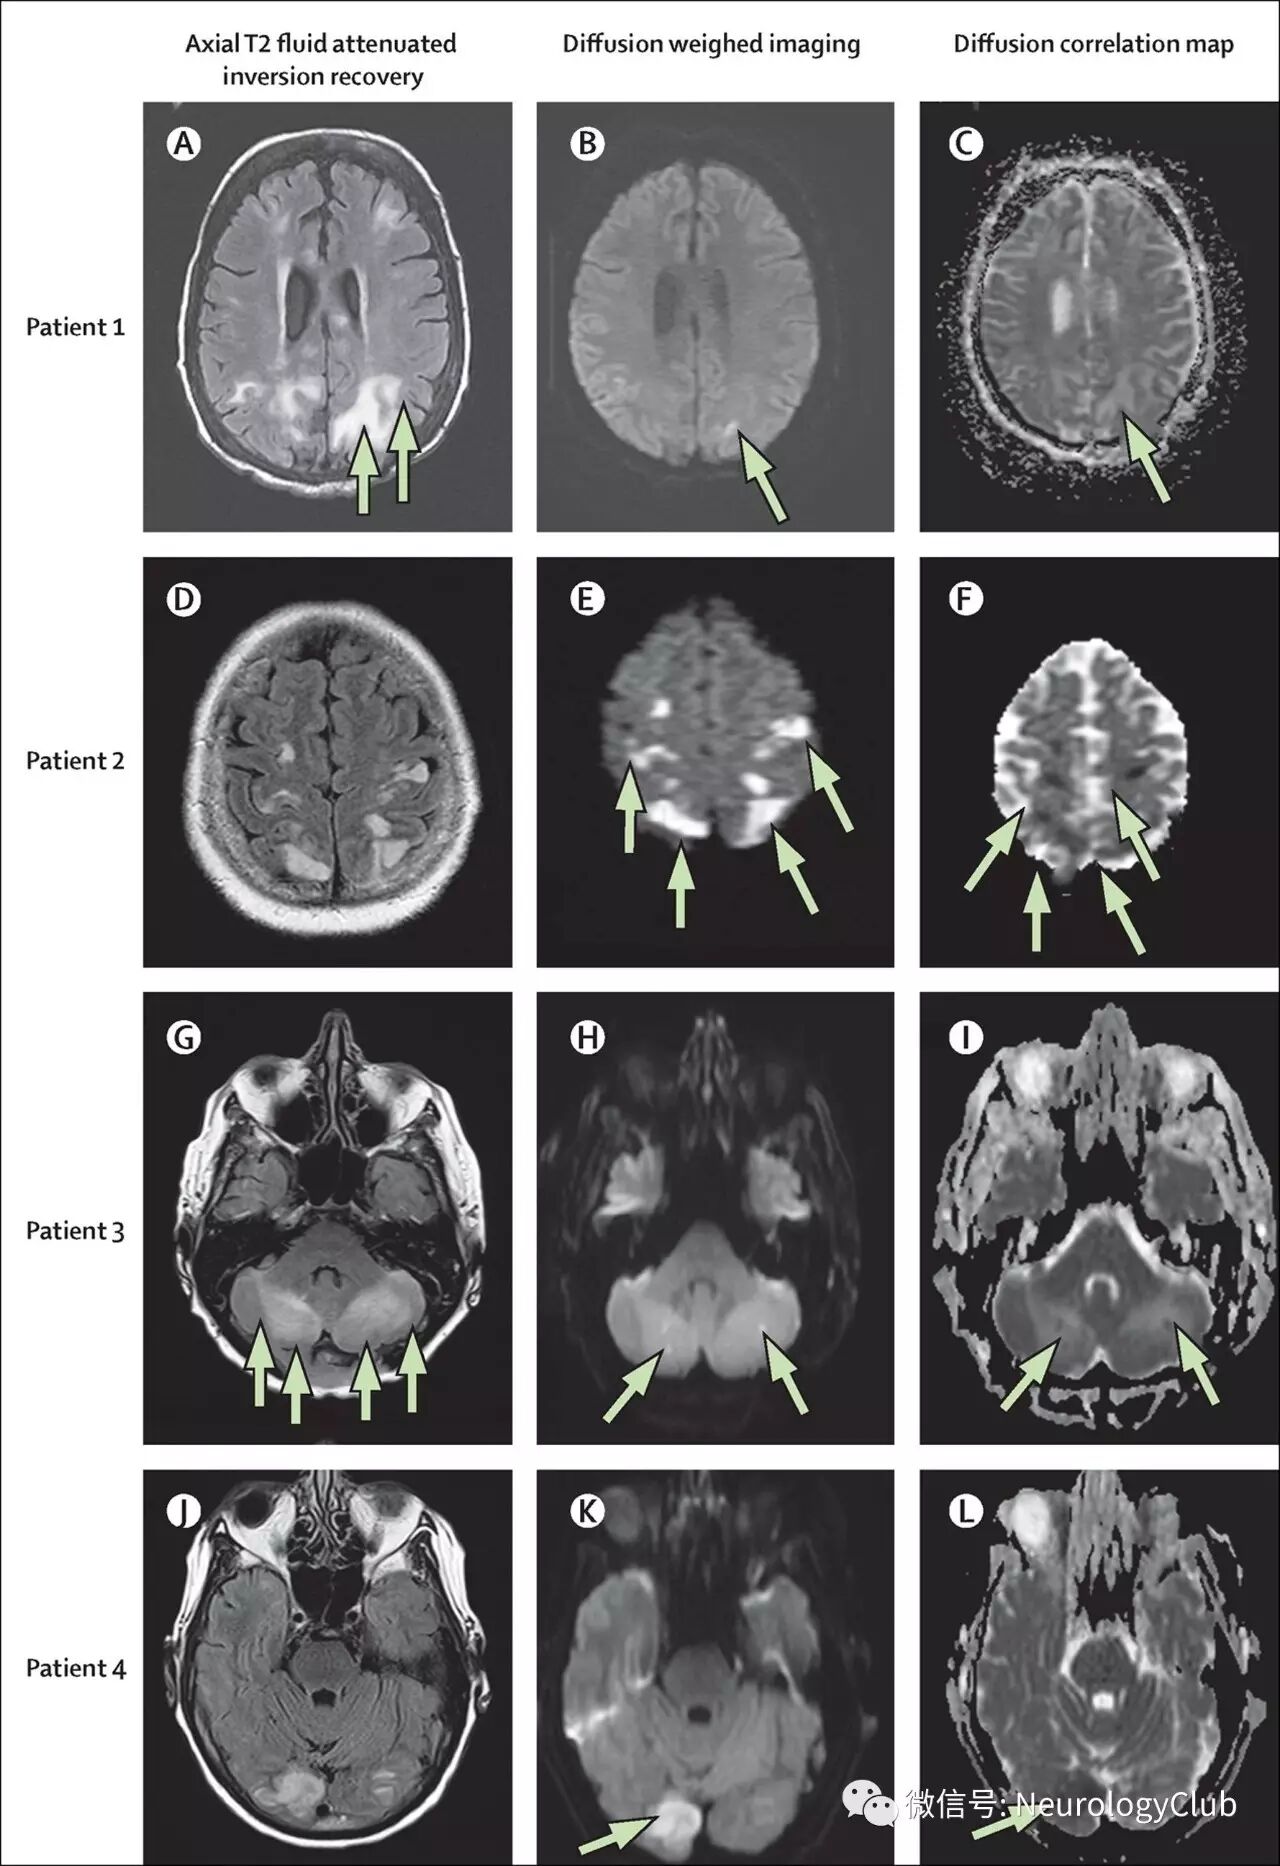

约15-30%患者在MRI上可见弥散受限。弥散受限部位通常是位于大片血管源性水肿部位的较小病灶。弥散受限病灶的出现通常与不可逆的损伤和临床不完全恢复相关。DWI高信号时,对应ADC值可低、等或高(见图5)。ADC值增加的区域根据T2透射效应(T2 shine-through effect)的数量在DWI上可表现为高、低或等信号。高ADC值病灶最可能是可逆的,而ADC值下降通常进展为真正的梗死。(注:T2透射效应即指DWI上的信号仍包含着T2弛豫时间的影响,因此DWI上的高信号病灶可能反应了强T2透射效应,而不是弥散减少。DWI低信号病灶是由于不能被T2效应平衡的更高ADC值所致)

(图5:PRES弥散受限表现)